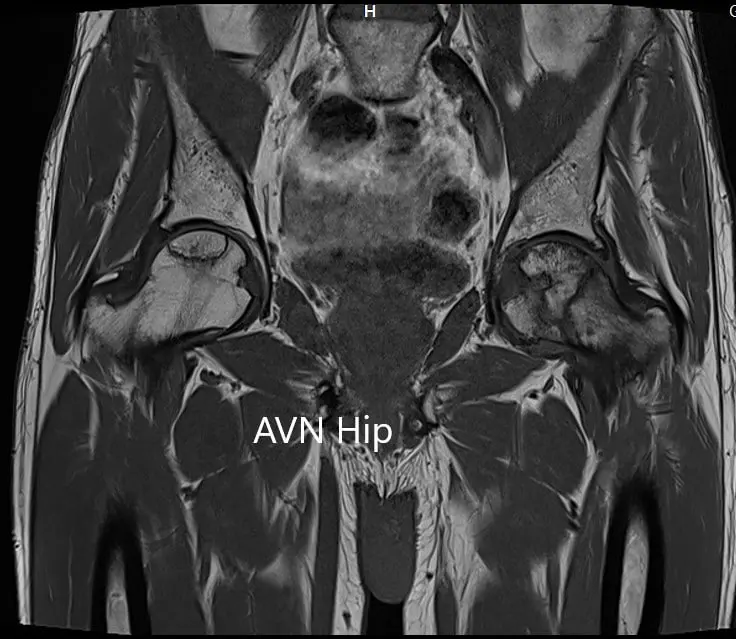

The left femoral head was collapsed with irregular contour and shows areas of altered signal intensity with a line of demarcation. Hypointense areas both on T1WI & T2WI seen in head suggestive of sclerosis. Surrounding marrow edema seen. A small amount of joint effusion with few osteophytes seen. The joint space was preserved.

The right femoral head shows areas of altered signal intensity with serpiginous demarcation line visualized, Hypointense areas both on T1WI & T2WI seen in head suggestive of sclerosis. The femoral head contour was normal. Surrounding marrow edema is seen. Small joint effusion is seen. Joint space is preserved.

Percentage necrotic areas in bilateral femoral heads are approximately 60-70 %.

T1WI coronal section of MRI showing AVN hip.